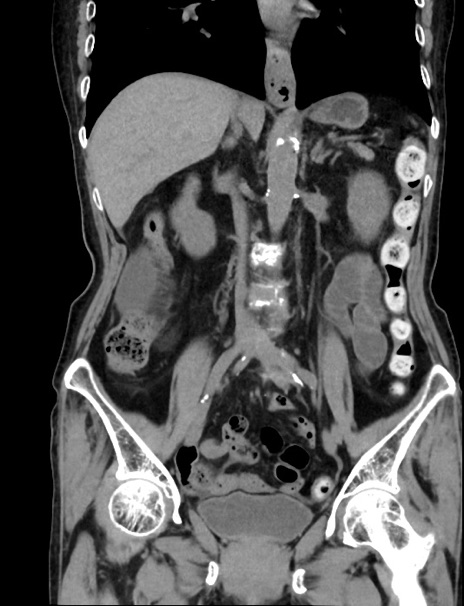

症例33(冠状断像)

【症例】70歳代 女性

【主訴】心窩部痛

【現病歴】延髄病変の精査・加療にて神経内科入院中。本日より心窩部痛あり。

【既往歴】虫垂炎

【身体所見】右下腹部を中心に圧痛と反跳痛あり。

【データ】WBC 10900、CRP 0.02

横断像